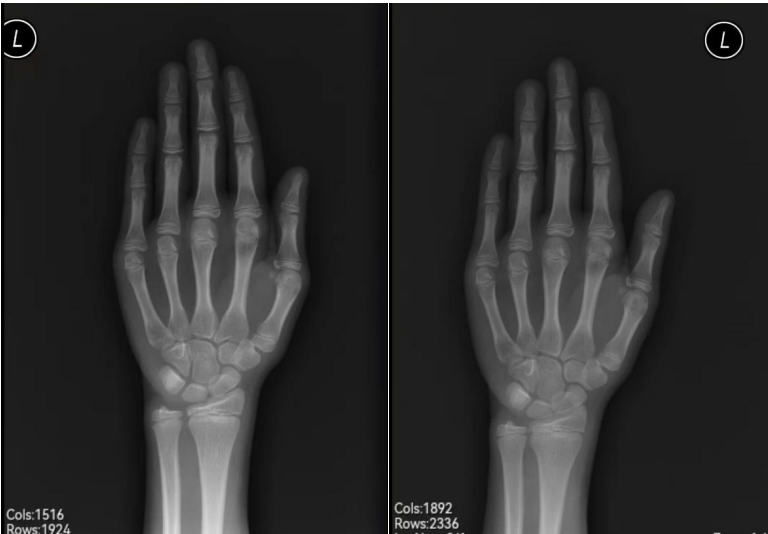

小蕾的妈妈一直比较关注女儿的身高发育,9岁来例假的时候就问过医生是不是过早发育,在10岁10个月的的时候做了骨龄测试,报告显示骨龄12岁,身高147cm是属于偏矮的。

▲左图为24年8月骨龄片;右图为25年2月拍摄骨龄片,正常发育